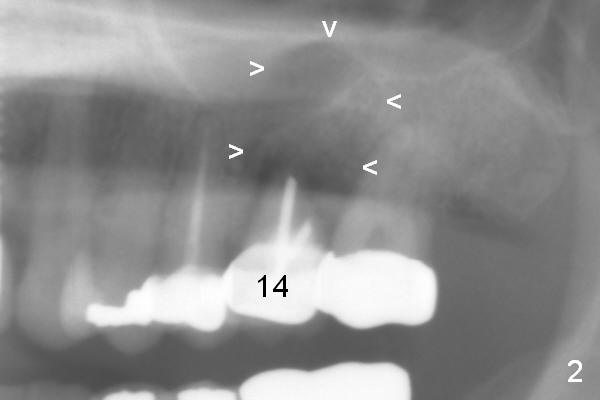

A 50-year-old woman has multiple restoration (Fig.1). She complains of upper left sensitivity. Exam shows that the tooth #14 has deep palatal pocket with purulent discharge. It appears that the palatal plate is lost (Fig.2 arrowhead). If it is confirmed after extraction (Clindamycin), an implant will be placed buccal to the center (septum). Collagen dressing or Osteotape (or preferably PRF if her veins are not too skinny) will be placed against the defective wall, followed by allograft. Use Magic Expanders or Sinus Lifter. Her bone is most likely not dense, since long implants are placed at #7-10.